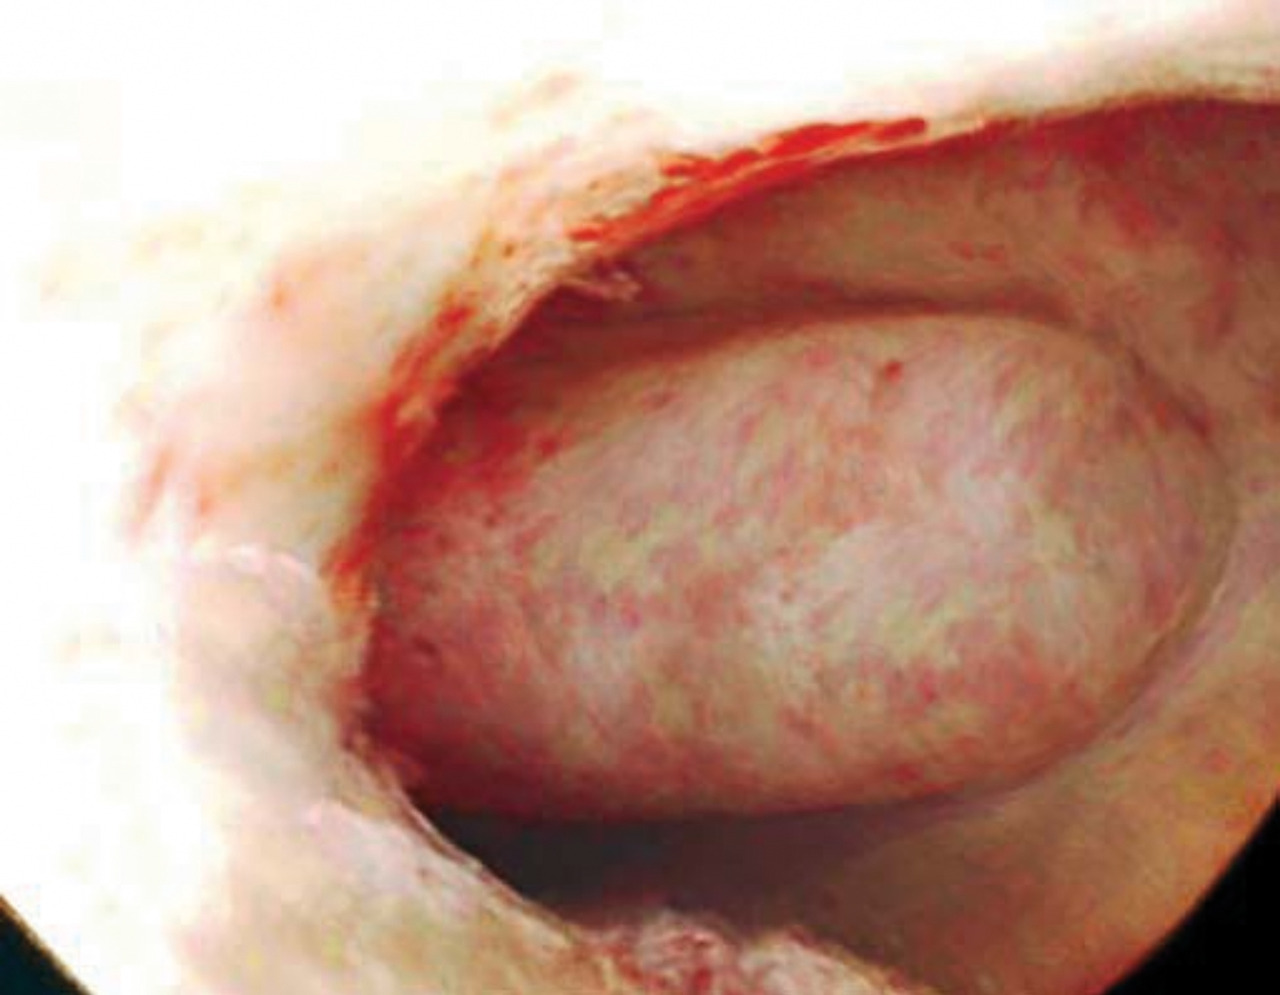

Le cancer du col utérin doit être évoqué, que les métrorragies soient provoquées par les rapports ou non. L’examen au spéculum recherche un aspect anormal du col, des lésions ulcérantes ou bourgeonnantes (fig. 8) évidentes à l’œil nu sur lesquelles sont pratiquées des biopsies. On réalise un frottis cervicovaginal et un test HPV de dépistage, puis des biopsies au cours d’une colposcopie, à la recherche d’un carcinome épidermoïde, le diagnostic reposant sur l’histologie.